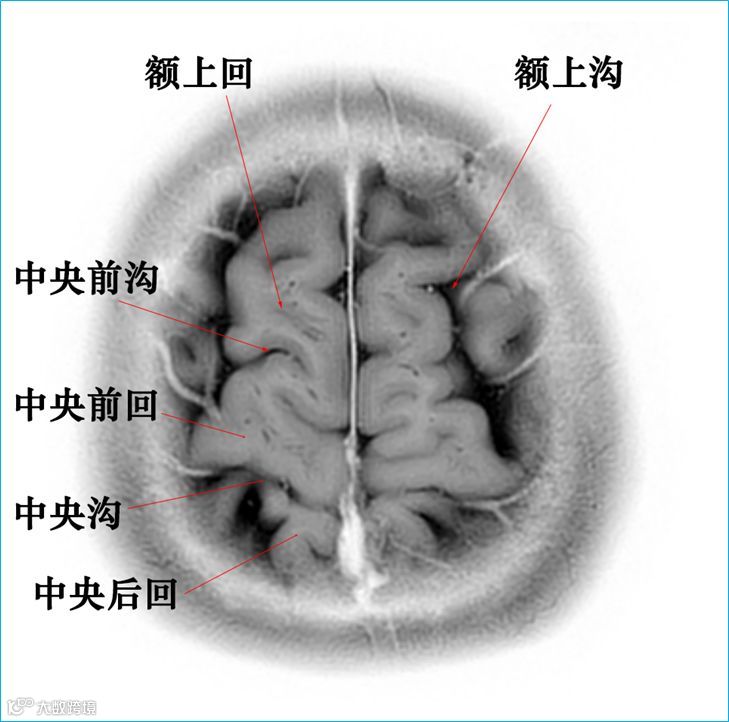

在T2WI反相图学下的颅脑断层解剖(吴晓安老师亲自手动标准)以及标本断层解剖,满满干货,坐在小板凳上,一起学习吧……